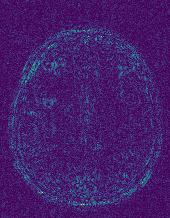

6.2.2 Quality of the Predicted Edges

EPN is utilized to provide edge priors for later reconstruction, so the quality of the predicted edges is very important. In Fig. 10, we provide some qualitative results of the predicted edges of EPN on three multi-coil datasets. Among them, the GT edges are extracted using the Sobel operator. As can be seen from the images, our proposed EPN can predict an approximate contour for the overall subject and can reconstruct accurate edges close to the GT edges under two acceleration factors. This fully verifies the effectiveness and excellence of the proposed EPN.